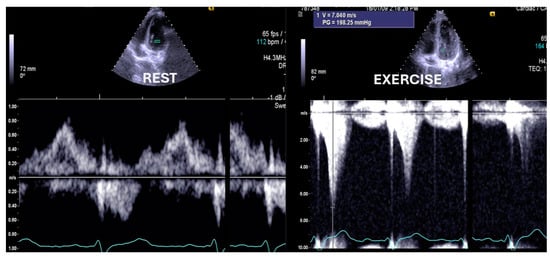

The ESEs for the 10 asymptomatic children whose screening was requested by their parents, 11 with symptoms unrelated to exercise, and 12 with antecedents of sudden death in the family showed normal results. The two children with previously intervened aortic coarctation revealed an increase in the aortic gradient, with reintervention required in one of them (Figure 7).

Figure 7.

Aortic gradient evaluated in a patient with aortic coarctation previously treated with a stent. Based on the exercise stress echocardiography results, the child was treated again [1].